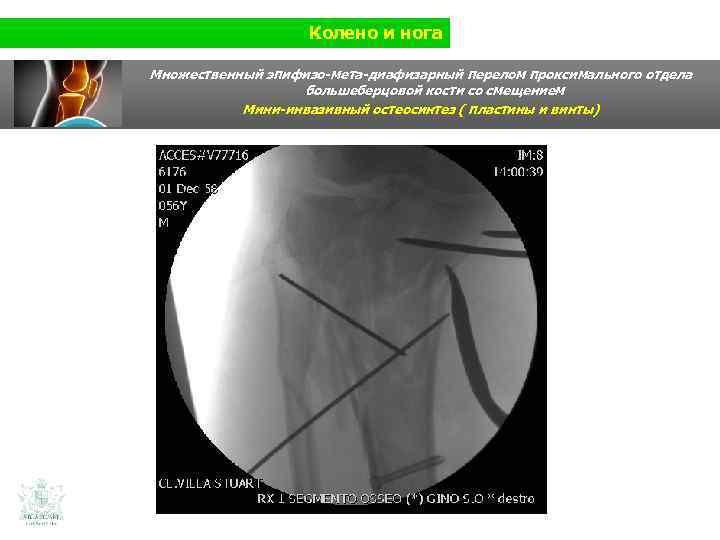

Колено и нога Множественный эпифизо-мета-диафизарный перелом проксимального отдела большеберцовой кости со смещением (Shatzer 6) Мини-инвазивный остеосинтез ( пластины и винты)

Колено и нога Множественный эпифизо-мета-диафизарный перелом проксимального отдела большеберцовой кости со смещением Мини-инвазивный остеосинтез ( пластины и винты)